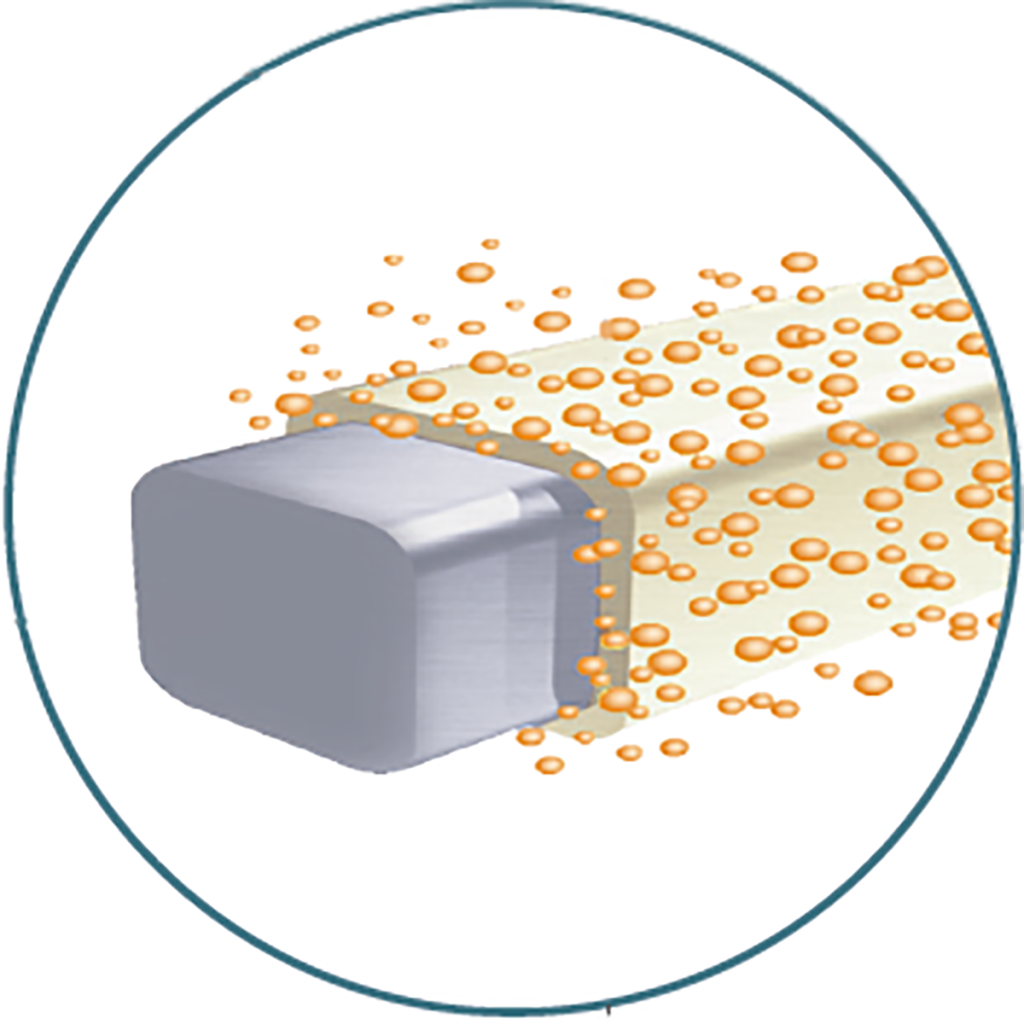

PLGA Biodegradable Polymer of Drug Coating

Drug completely release in 90 days

PLGA coating completely degraded in 180 days

Microscopic view of stable drug coating for GuReater ™ during degradation